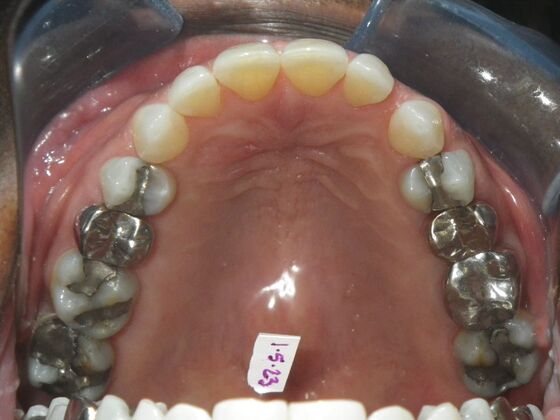

Patient wanted to close all spaces, especially upper right by her cuspid.